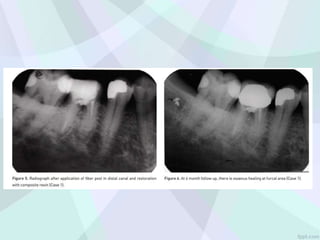

Repair of FurcalIatrogenic Perforation with Mineral Trioxide Aggregate

FOLLO UP :3 YEAR